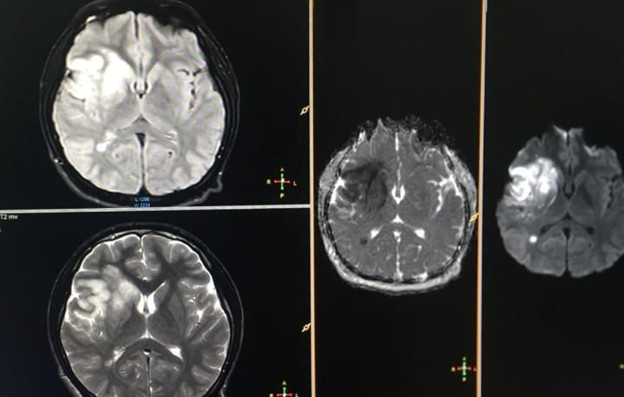

A non-contrast CT scan initially provided inconclusive results, prompting diffusion-weighted MR brain imaging, revealing an acute middle cerebral artery stroke (Figure 1). Subsequent MRI brain with MR venography demonstrated additional findings, including asymmetrical cavernous sinus and narrowed right internal carotid artery (Figure 2). Consequently, MRA of the carotid vasculature revealed a hypoplastic right internal carotid artery and abnormal appearances of the middle cerebral and anterior cerebral arteries, presenting as a beaded appearance at the petrous (C2), lateral, and cavernous (C4) segments, with collateral filling through the circle of Willis (Figure 3).

Figure1. Axial sections of the brain, including Flair, T2, and ADC/DWI sequences, reveal an acute MCA infarct.